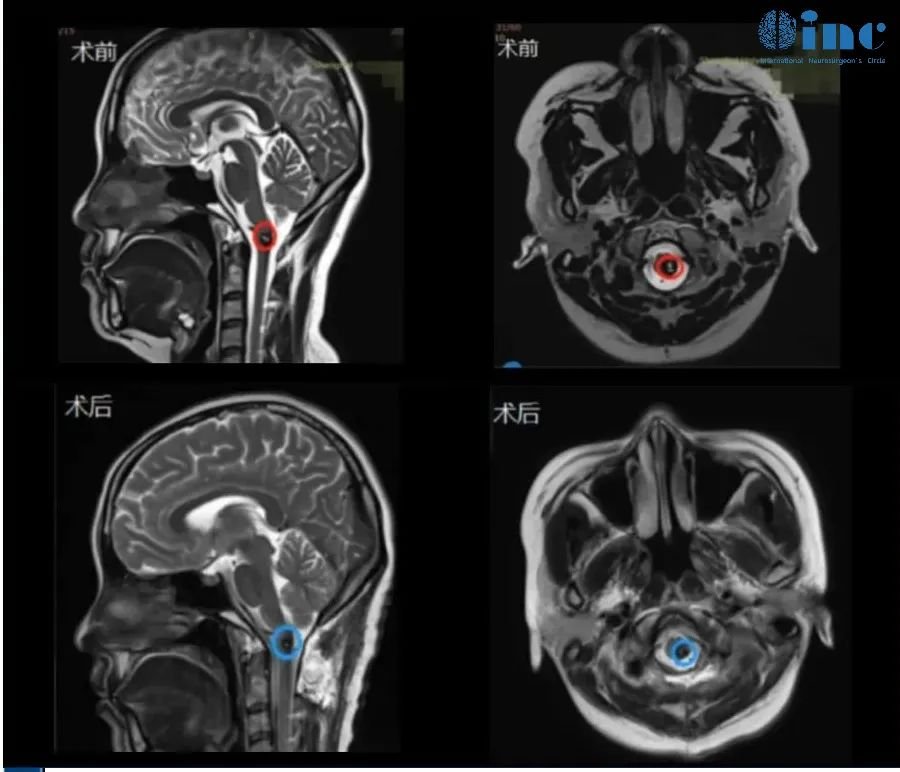

◉患者情况:24岁的川川于 2019 年中出现无明显诱因的左侧上肢无力,随后伴有头晕头痛症状。进行头颅核磁检查提示:延髓后方结节性病灶。医生建议随诊复查,未做不同治疗。随后症状自行缓解。2023 年以来,小海出现了左侧下肢无力,大约两周后自行缓解。随后出现一过性拖地行走,双眼视力下降,偶有复视。近半年,患者偶有呼吸频率改变,一过性呼气吸气变浅,舌尖麻木。4 月份后,患者自感左脚及双侧脸颊麻木、舌尖麻木。

◉治疗经过:巴特朗菲教授带领国内神经外科手术团队经过紧张奋战,尽最大的努力切除肿瘤,完全保护延髓神经血管,无任何新发神经功能损伤。

◉术后情况:术后当天ICU巴教授查房,意识清醒、状态良好,对答如流,可以咳嗽、吞咽功能都正常,术前双手麻木仍存在。术后一天普通病房查房:手指麻木好转,结果都好。川川对巴教授说:"So hungry!"并询问巴教授是否有饮食禁忌。巴教授表示:什么都可以吃,只要你想。术后二天查房:已经下床四处走走。目前距离手术过去2个月,川川状态良好,已经逐渐恢复了正常的工作和学习。